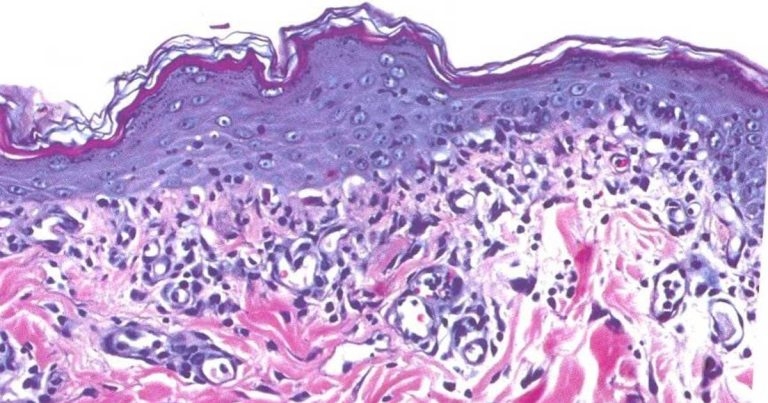

Figure 1. Interface dermatitis. The epidermis is thickened, apoptotic keratinocytes are present and a band of lymphocytes is present in the upper dermis.

The consequences of the lymphocytic attack are more or less symmetrical erythema, erosion, ulceration, depigmentation and crusting. It is very unusual to see evidence of systemic disease in dogs with a CLE variant. The histopathological findings are characterised by a lymphocyte-rich infiltrate into the upper dermis, a lupoid band, associated with single cell apoptosis – an interface dermatitis (Figure 1).

A lichenoid infiltrate describes a superficial band-like pattern of lymphocytes and plasma cells in the upper dermis. It may be more or less normal underneath a mucosal surface, and may be noted beneath a superficial infection. An interface reaction describes a lichenoid, cell-rich, lymphocytic interface dermatitis, with basal keratinocyte vacuolar degeneration and apoptosis.